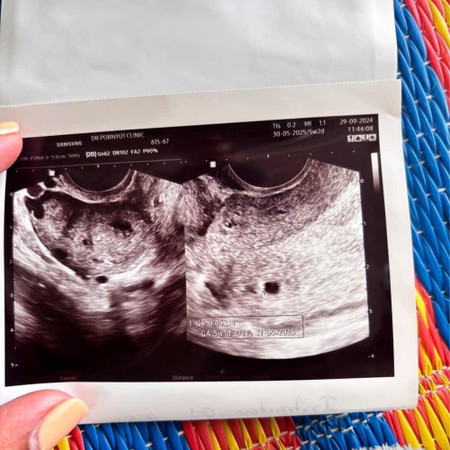

5W1D ขนาดถุงตั้งครรภ์ปกติมั้ยค่ะ

สอบถามแม่ๆค่ะ ขนาดถุงตั้งครรภ์เท่านี้ปกติไหมคะ 5W1D

ปกติค่ะ นี้ตอน5วีคค้ะอัลตร้าซาวด์ครั้งแรก ตอนนี้ 26 วีคแล้วค่ะ ซนแล้วด้วย